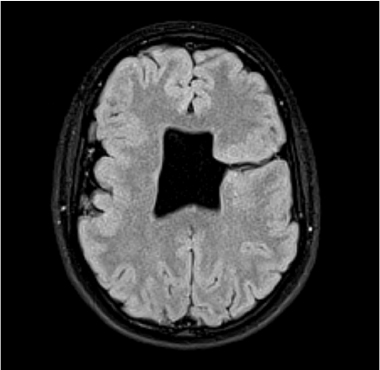

Periventricular Heterotopias (PV) are groups of misplaced neurons that line the ventricles. It’s presumed that the neurons, which are produced in the periventricular area, fail to migrate up into the developing neocortex and instead get stuck in the germinal zone. Below are examples from Tuberous Sclerosis (left) with similar kinds of tuberous growths that surround the ventricles of the brain, and PVs found in idiopathic autism (right).